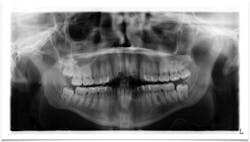

Figure 3: Radiograph from patient’s initial exam

A healthy 22-year-old female patient presented for a comprehensive examination (figure 3). She had no chief complaints and no caries. The patient was referred to an oral surgeon for removal of wisdom teeth. Following that, all contact was lost.